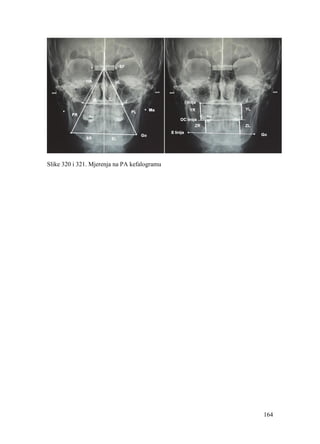

3. Jena AK, Duggal R, Parkash H. Skeletal and dentoalveolar effects of Twin-block and

bionator appliances in the treatment of Class II malocclusion: a comparative study.